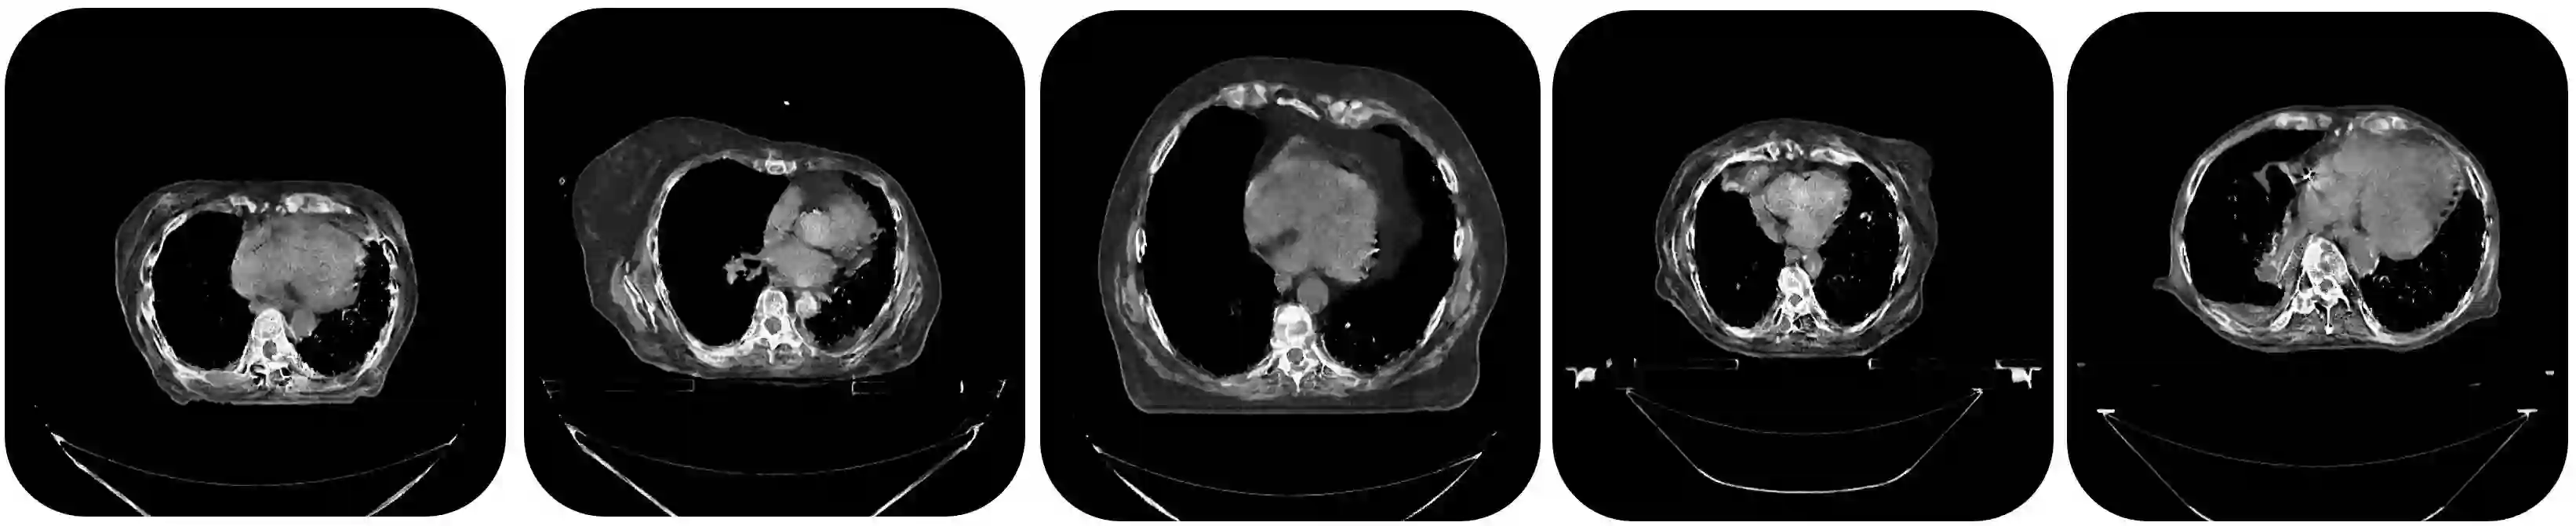

Deep learning has shown great promise for CT image reconstruction, in particular to enable low dose imaging and integrated diagnostics. These merits, however, stand at great odds with the low availability of diverse image data which are needed to train these neural networks. We propose to overcome this bottleneck via a deep reinforcement learning (DRL) approach that is integrated with a style-transfer (ST) methodology, where the DRL generates the anatomical shapes and the ST synthesizes the texture detail. We show that our method bears high promise for generating novel and anatomically accurate high resolution CT images at large and diverse quantities. Our approach is specifically designed to work with even small image datasets which is desirable given the often low amount of image data many researchers have available to them.